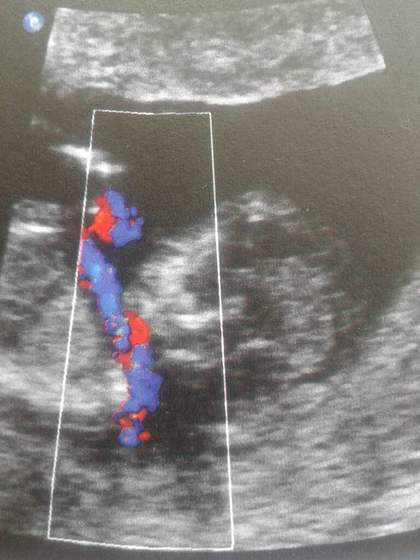

Indi widzialam zdjecie twojego usg i mi to na chlopczyka wygląda :)

Dziewczyna na watku o planowaniu wyglada to na chlopczyka, ale ja wciaz mam nadzieje na swoja wymarzona córeczkę.

Tutaj fotka jak lezy na pepowinie

Załączniki

• 1405937696554.jpg